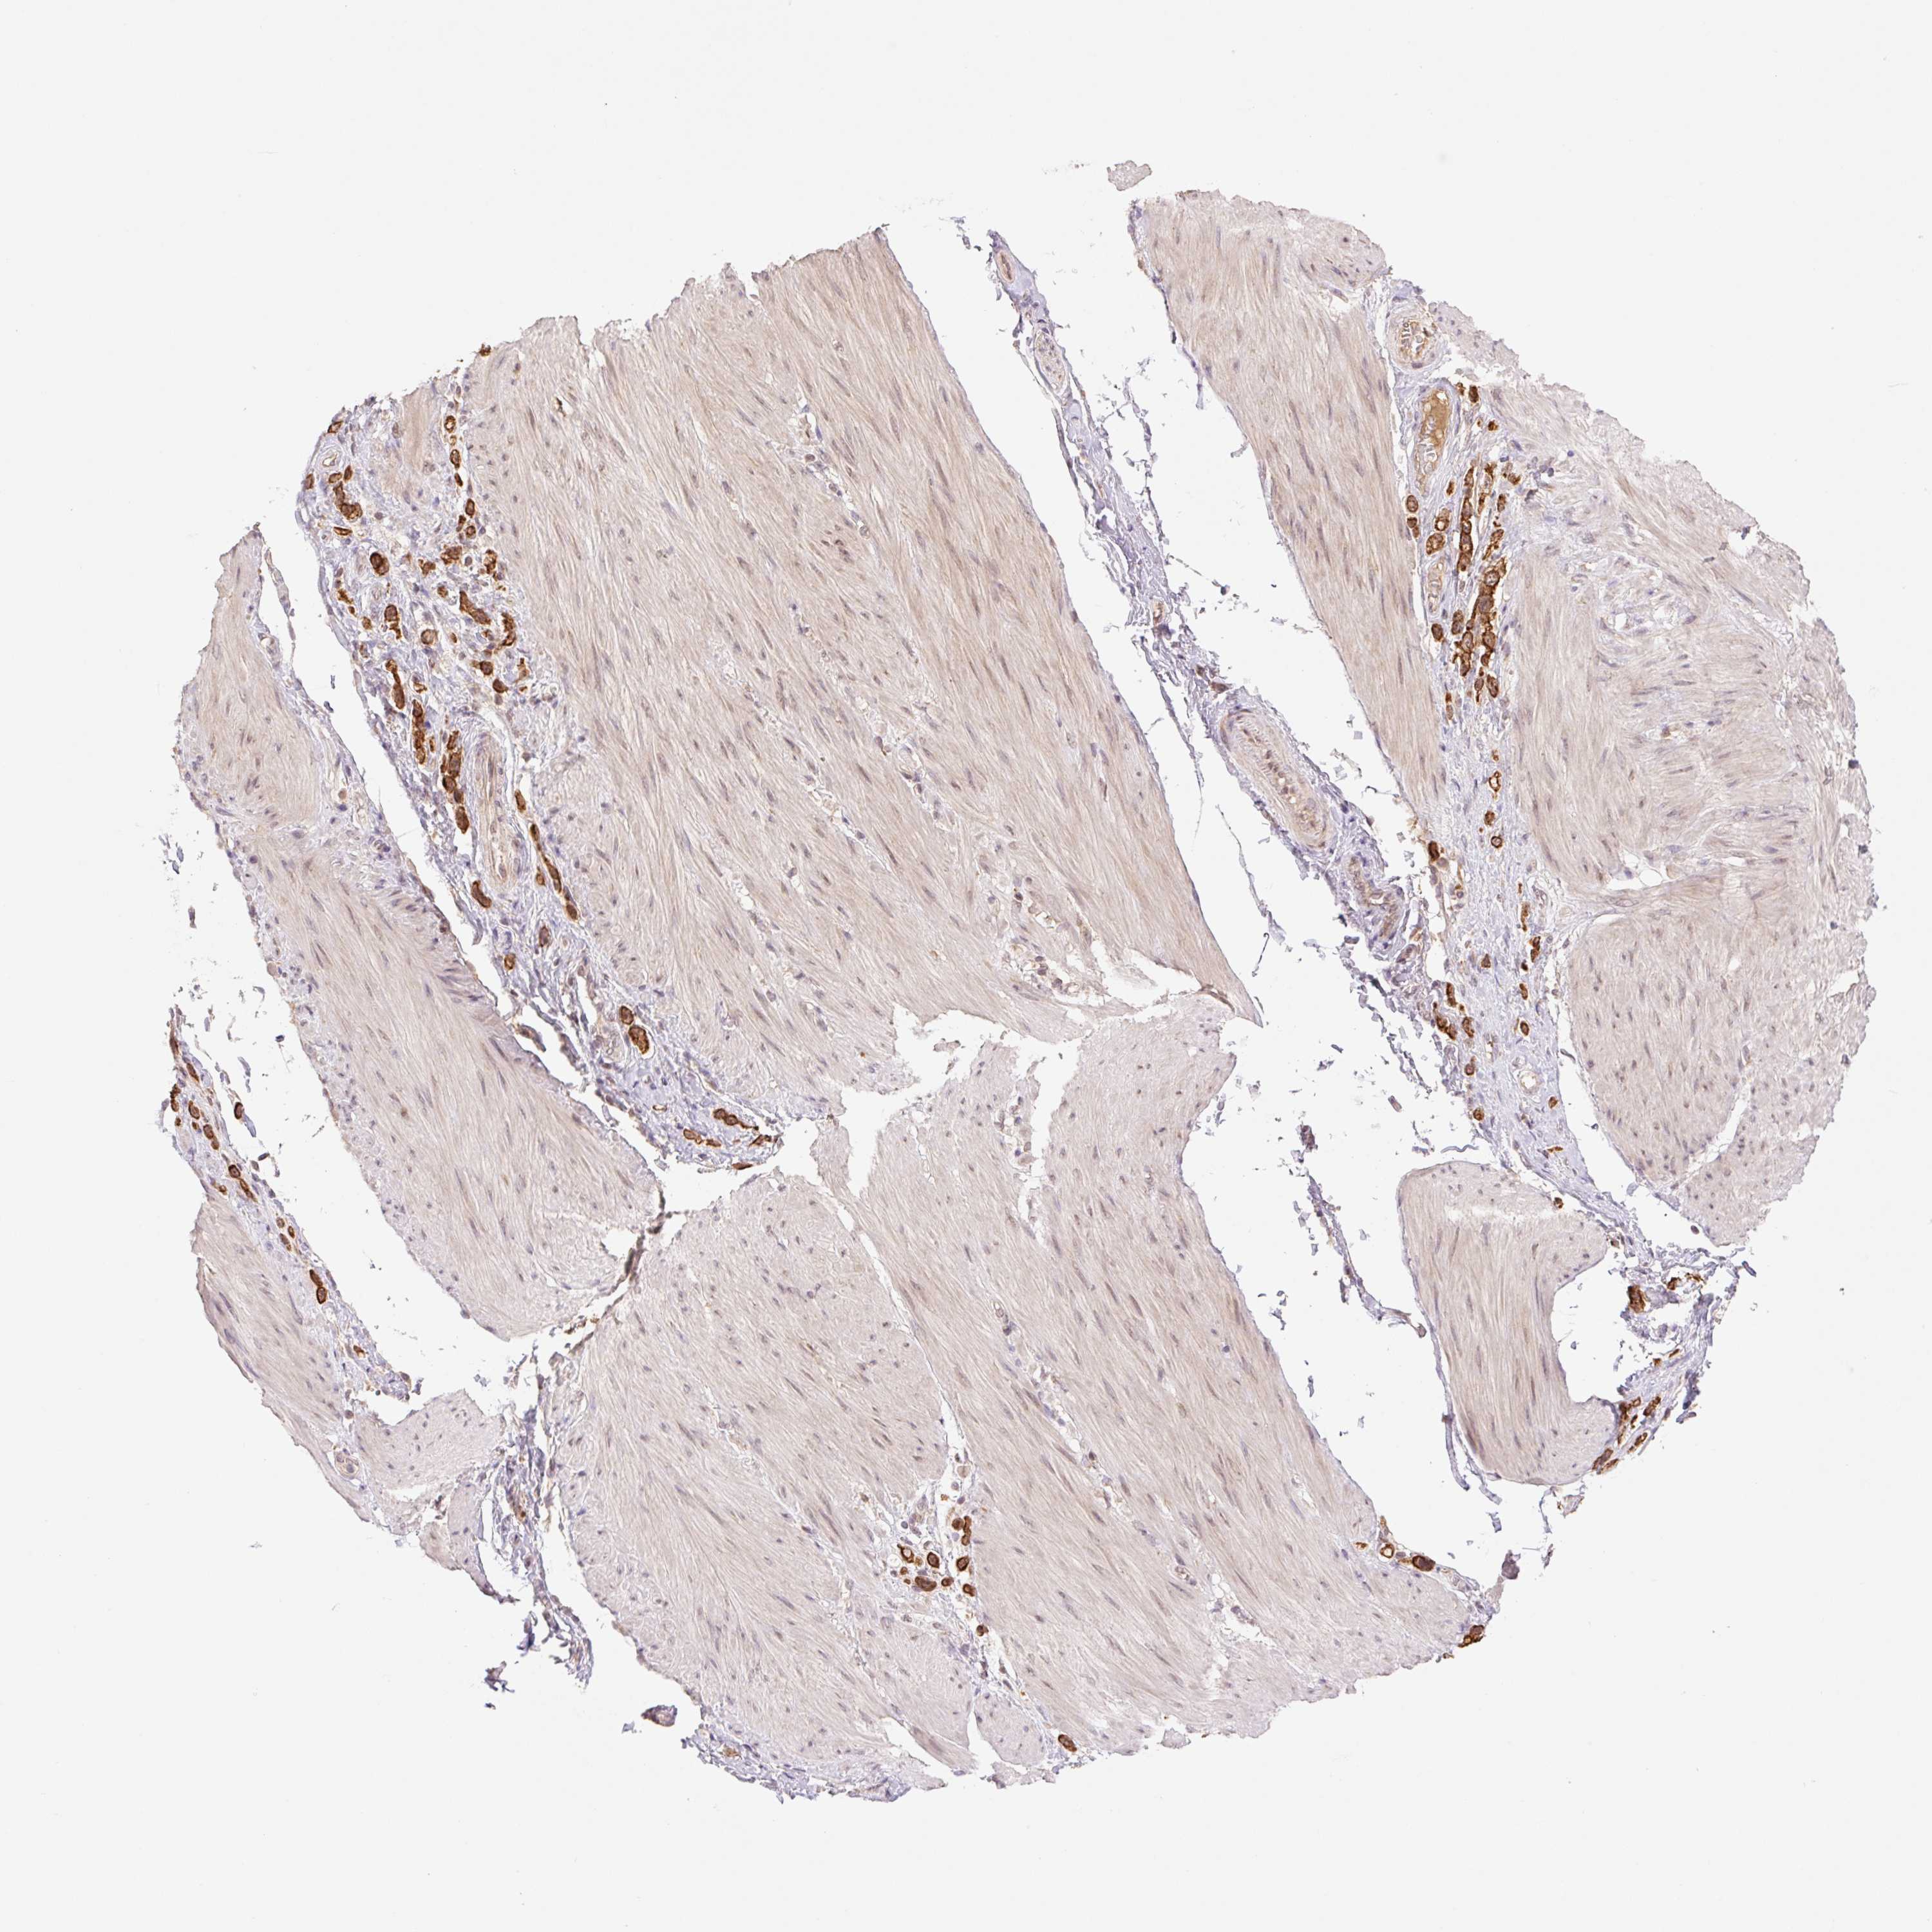

STOMACH CANCER - Protein expressioni

A mouse-over function shows sample information and annotation data. Click on an image to view it in a full screen mode. Samples can be filtered based on level of antibody staining by selecting one or several of the following categories: high, medium, low and not detected. The assay and annotation is described here.

Note that samples used for immunohistochemistry by the Human Protein Atlas do not correspond to samples in the TCGA dataset.

Antibody stainingi

Antibody staining in the annotated cell types in the current human tissue is reported as not detected, low, medium, or high, based on conventional immunohistochemistry profiling in selected tissues. This score is based on the combination of the staining intensity and fraction of stained cells.

Each image is clickable and will lead to virtual microscopy that enables deeper exploration of all samples and also displays staining intensity scores, fraction scores and subcellular localization as well as patient and tissue information for each sample.

Antibody HPA056977

Staining

High

Medium

Low

Not detected

Intensity

Strong

Moderate

Weak

Negative

Quantity

>75%

75%-25%

<25%

None

Location

Nuclear

Cytoplasmic/membranous

Cytoplasmic/membranous,nuclear

Adenocarcinoma, NOS